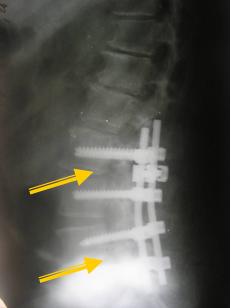

У таких случаях выполняется межтеловой спондилодез и транспедикулярная фиксация.

2. Микродискэктомия с одномоментной стабилизацией ПДС — это операция, которая выполняется при сочетании грыжи диска и нестабильности [►] позвоночника на уровне грыжи или на смежных уровнях. Другими словами, когда есть нестабильность (патологическая подвижность) конкретного ПДС, подтверждаемая функциональными рентгеновскими пробами, в сочетании с «хирургической» грыжей диска, выполнение только микродискэктомии в данном случае не только противопоказано, но и опасно в плане дальнейшего нарастания нестабильности позвоночника и стойкого хронического послеоперационного болевого синдрома. Микродискэктомия с одномоментной стабилизацией позвоночно-двигательного сегмента выполняется нечасто, но подобный дифференцированный индивидуальный подход позволяет уверенно сохранить опорную функцию позвоночника у всех больных, страдающих сочетанием грыжи диска с нестабильностью.